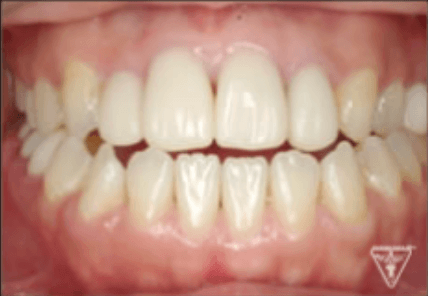

治療後